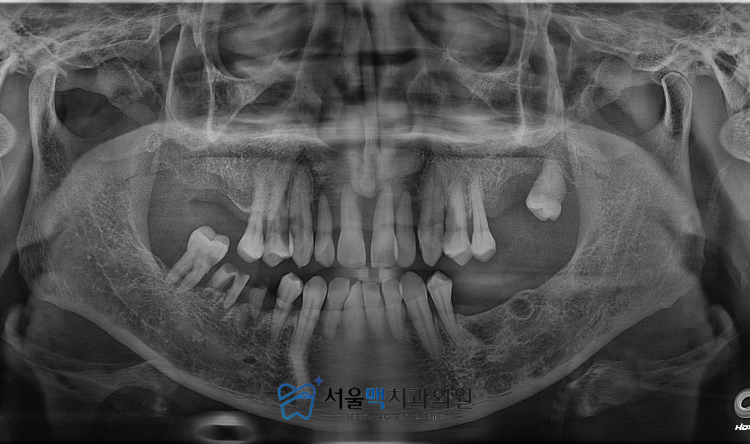

이번에 가양역치과 서울맥치과를 내원하신 환자분은

구강 내에 대다수의 치아가 남아있는 상태였으나

치아를 거의 사용하지 못하고 계셨습니다.

정밀 진단을 통해 확인한 결과

가양역치과 환자분의 치주 상태는

매우 심각한 수준이었습니다.

겉으로 보기에는 치아들이

자리를 지키고 있는 것처럼 보였지만

실제로는 치아를 지탱해 주어야 할

치조골이 대부분 소실되어

치아들이 흔들리고 있었습니다.

잇몸 질환으로 인해 염증이 진행된 치아들은

음식을 씹는 작은 힘조차 견디지 못하는 상태였고

이로 인해 환자분은 오랫동안

제대로 된 식사를 하지 못해

전신 건강까지 우려되는 상황이었습니다.